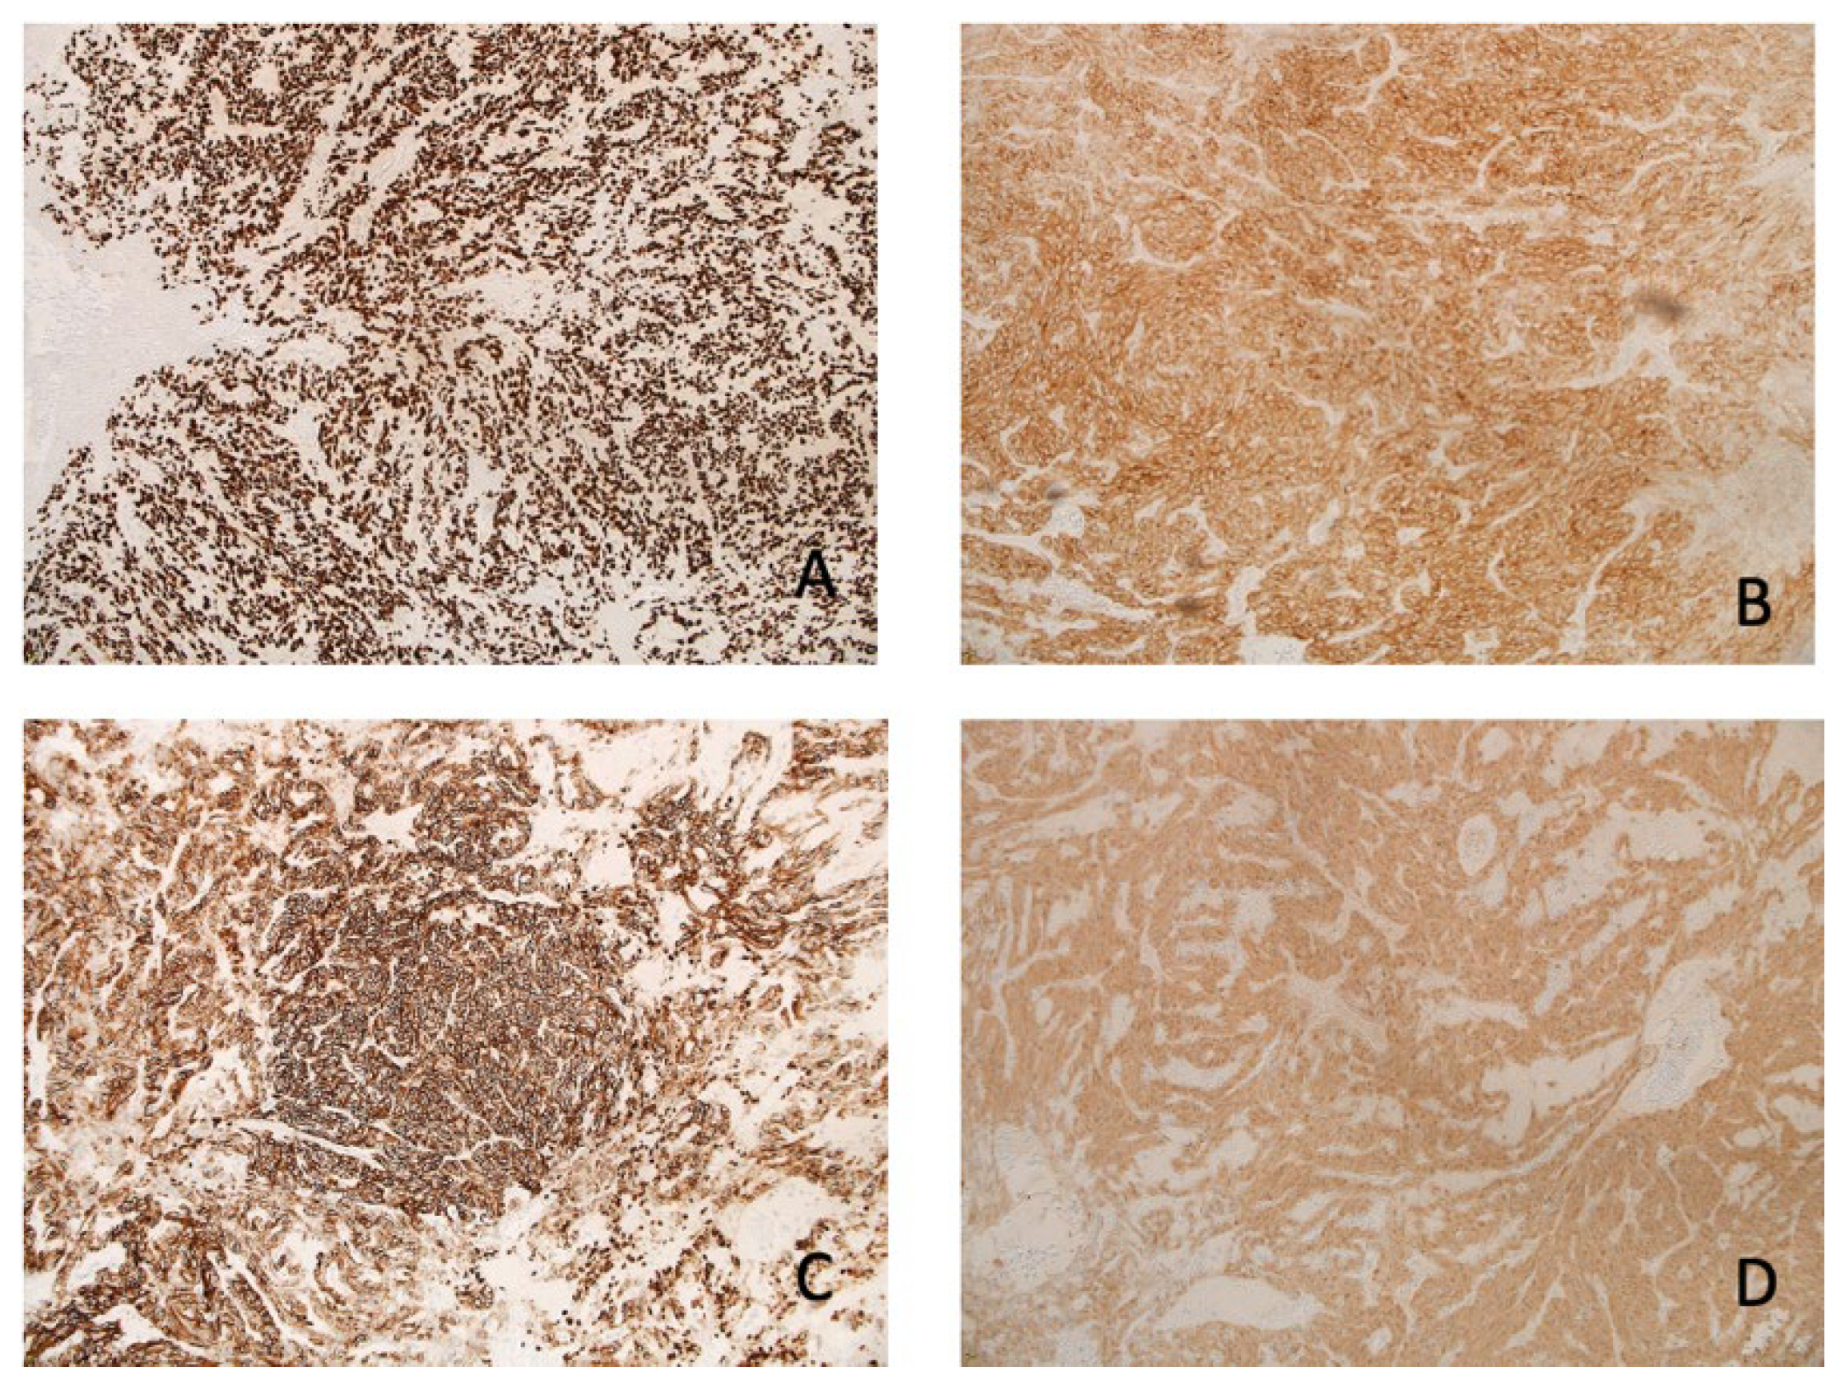

2. Case Presentation